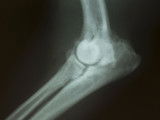

Les os des chiens affectés présentent un défaut de minéralisation et prennent une forme assez caractéristique, dite en « bouchon de champagne ». La boiterie du chien, généralement discrète, peut être accompagnée de douleurs au niveau de l'articulation, surtout lors des manipulations du membre souffrant. Ce sont souvent les jointures qui sont touchées, comme le genou, l'épaule ou le grasset. Le chien a aussi tendance à ne poser que la plante des pattes au sol, et montre un retard général de croissance. Il peut également souffrir de troubles digestifs (vomissements, diarrhées...), se montrer difficile lors des repas ou encore manquer d'entrain.